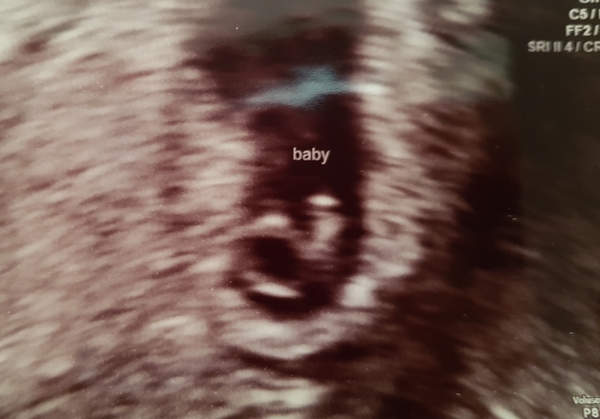

clairehr · 25/06/2018 17:40

Thank you all for being so supportive!

I know it doesn't look like much but this right here is mine 😍 I'm a little bit in love right now!

Hope everyone doing ok today, I'm spreading a whole load of positivity over the group!

@clairehr That's so lovely to see! Thanks for sharing. How many weeks & days are you now? I'm sure you've said below but I am rubbish at remembering!

clairehr · 25/06/2018 18:04

@RedRobin7 I'm 6+1 with baby measuring exactly that at 4.6mm. Sooo tiny, but so special!